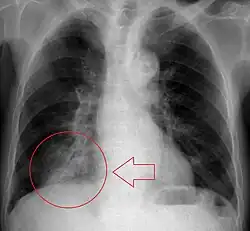

Diagnostic Imaging

Radiography is the most common form of imaging used in the initial assessment of a foreign body presentation. Most patients receive a chest x-ray to determine the location of the foreign body.[2] Lateral neck, chest, and bilateral decubitus end-expiratory chest x-rays should be obtained in patients suspected of having aspirated a foreign body.[6] However, the presence of normal findings on chest radiography should not rule out foreign body aspiration as not all objects can be visualized.[2] In fact, up to 50% of cases can have normal findings on radiography.[7] This is because visibility of an object depends on many factors, such as the object's material, size, anatomic location and surrounding structures, as well as the patient's body habitus.[13] X-ray beams only show an object if that object's composition blocks the rays from traveling through, making it radiopaque and appearing lighter or white on the image. This also requires it to not be stuck behind something that blocks the beams first.[13] Objects that are radiopaque include items made of most metals except aluminum, bones except most fish bones, and glass. If the material does not block the x-ray beams it is considered radiolucent and will appear dark which prevents visualization.[13] This includes material such as most plastics, most fish bones, wood, and most aluminum objects.[13]

Other diagnostic imaging modalities, such as magnetic resonance imaging, computed tomography, and ventilation perfusion scans play a limited role in the diagnosis of foreign body aspiration.[7]

Signs on x-ray that are more commonly seen than the object itself and can be indicative of foreign body aspiration include visualization of the foreign body or hyperinflation of the affected lung.[13] Other x-ray findings that can be seen with foreign body aspiration include obstructive emphysema, atelectasis, and consolidation.[8]

While, x-ray can be used to visualize the location and identity of a foreign body, rigid bronchoscopy under general anesthesia is the gold-standard for diagnosis since the foreign body can be visualized and removed with this intervention.[2] Rigid bronchoscopy is indicated when two of the three following criteria are met: report of foreign body aspiration by the patient or a witness, abnormal lung exam findings, or abnormal chest x-ray findings.[2]